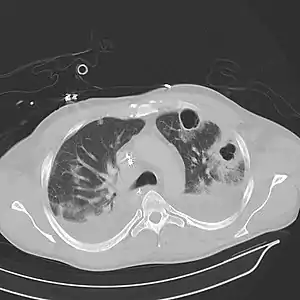

| Computed tomography (CT) scan of chest showing bilateral pneumonia with abscesses, effusions, and caverns. 37-year-old male. | |